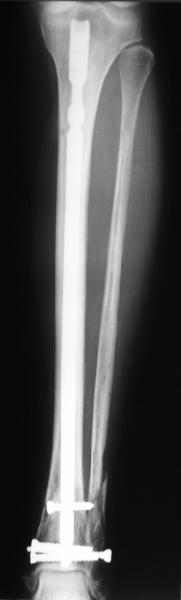

TDVC> Very interesting application, but is the final position in a

TDVC> little distal varus with some fibula distraction?

At least both the ankle mortise and tibial alignment look acceptable, don't they?

TDVC> Would that have been eliminated by fibula plating?

I am just trying to illustrate that prevention of 1)tibial valgus and 2)loss of reduction can be provided without fibular plating. Small changes of conventional nailing techniques allow to maintain reduction of the tibia reliably without adjunctive fibular stabilization.

In delayed cases acute length restoration performed only in the tibia may leave the fibula shortened thus change the mortise. So it is reasonable to restore length of both bones simultaneously by distractor and fix the fibula not with open reduction and plating but just by a single perQ screw. Example attached.